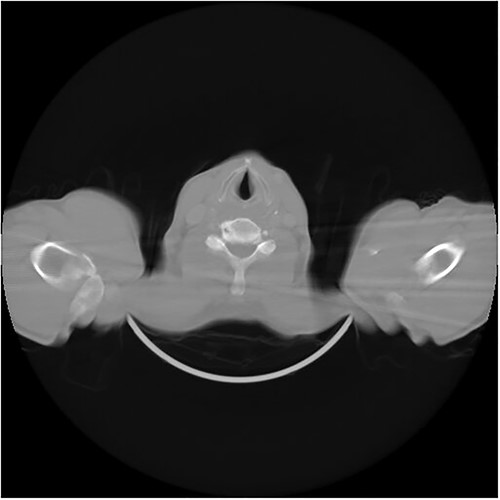

A 63-year-old male presented with a 1-year history of dysphonia, hoarseness, choking, progressive dysphagia, and a sensation of throat obstruction. The patient, a smoker, denied cough and weight loss. Family history was unremarkable. Physical examination revealed no specific features, and there was no evidence of lymphadenopathy or distant metastasis. The strobolaryngoscopy was performed and a mass above the left vocal cord was identified (Fig. 1) (Video S1). The mass was completely resected using micro scissors under general anesthesia, with visualization using a microscope attached to the laryngoscope, and was subjected to pathologic examination. A gross examination of the resected mass revealed multiple fragments measuring 7 cm in maximum diameter (Fig. 2). Microscopically, there was diffuse and nodular proliferation of bland fusiform or stellate neoplastic cells in a myxoid stroma (Fig. 3A). The fibrotic areas are more cellular but the cells themselves appear similar to those in the myxoid areas (Fig. 3B). Tumor cells have small hyperchromatic nuclei (Fig. 3C and D). Mitotic figures are rare. In immunohistochemistry, cytokeratin is negative (Fig. 4A). Ki67 rate is very low (Fig. 4B and C). Tumor cells show positivity to vimentin (Fig. 4D). The diagnosis of LGFMS was made. After a follow-up period of 6 months, the patient had no signs of tumor recurrence or metastases, as confirmed by a computed tomography (CT) scan (Fig. 5).

CT scan of the neck and throat image shows no signs of tumor recurrence or metastases.